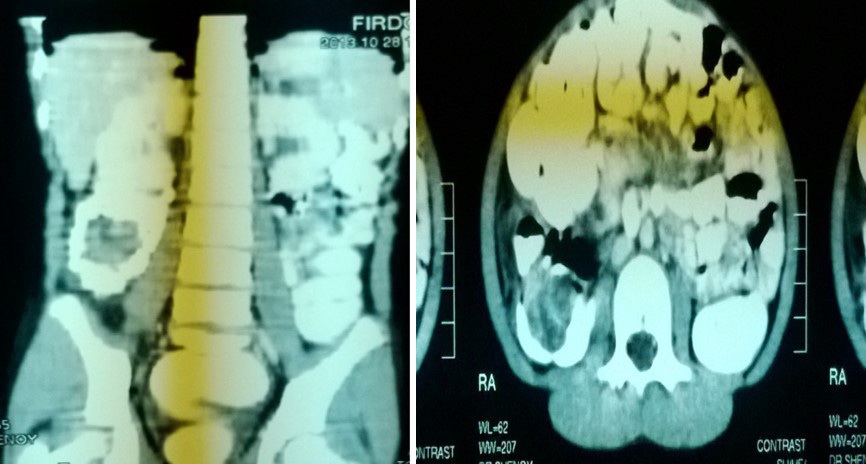

Computer tomograpahy:

• CT was done in 2 of our cases

• 1 case of PEUTZ JEGHERS SYNDROME

• 1 case was of chronic intussusception with benign polyp as lead point in ascending colon

Chronic intussusception:

• 12 years old female patient presented with chronic abdominal pain since 6 months.

• USG ABDOMEN-WNL.

• CT ABDOMEN.